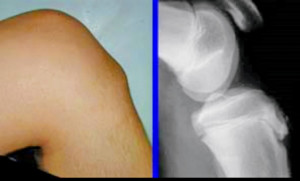

オスグッド

成長痛(オスグッド/シーバー/ジャンパー/シンスプ/外脛骨障害)のお悩みまとめ

osgood

成長痛に悩む人は読んでください